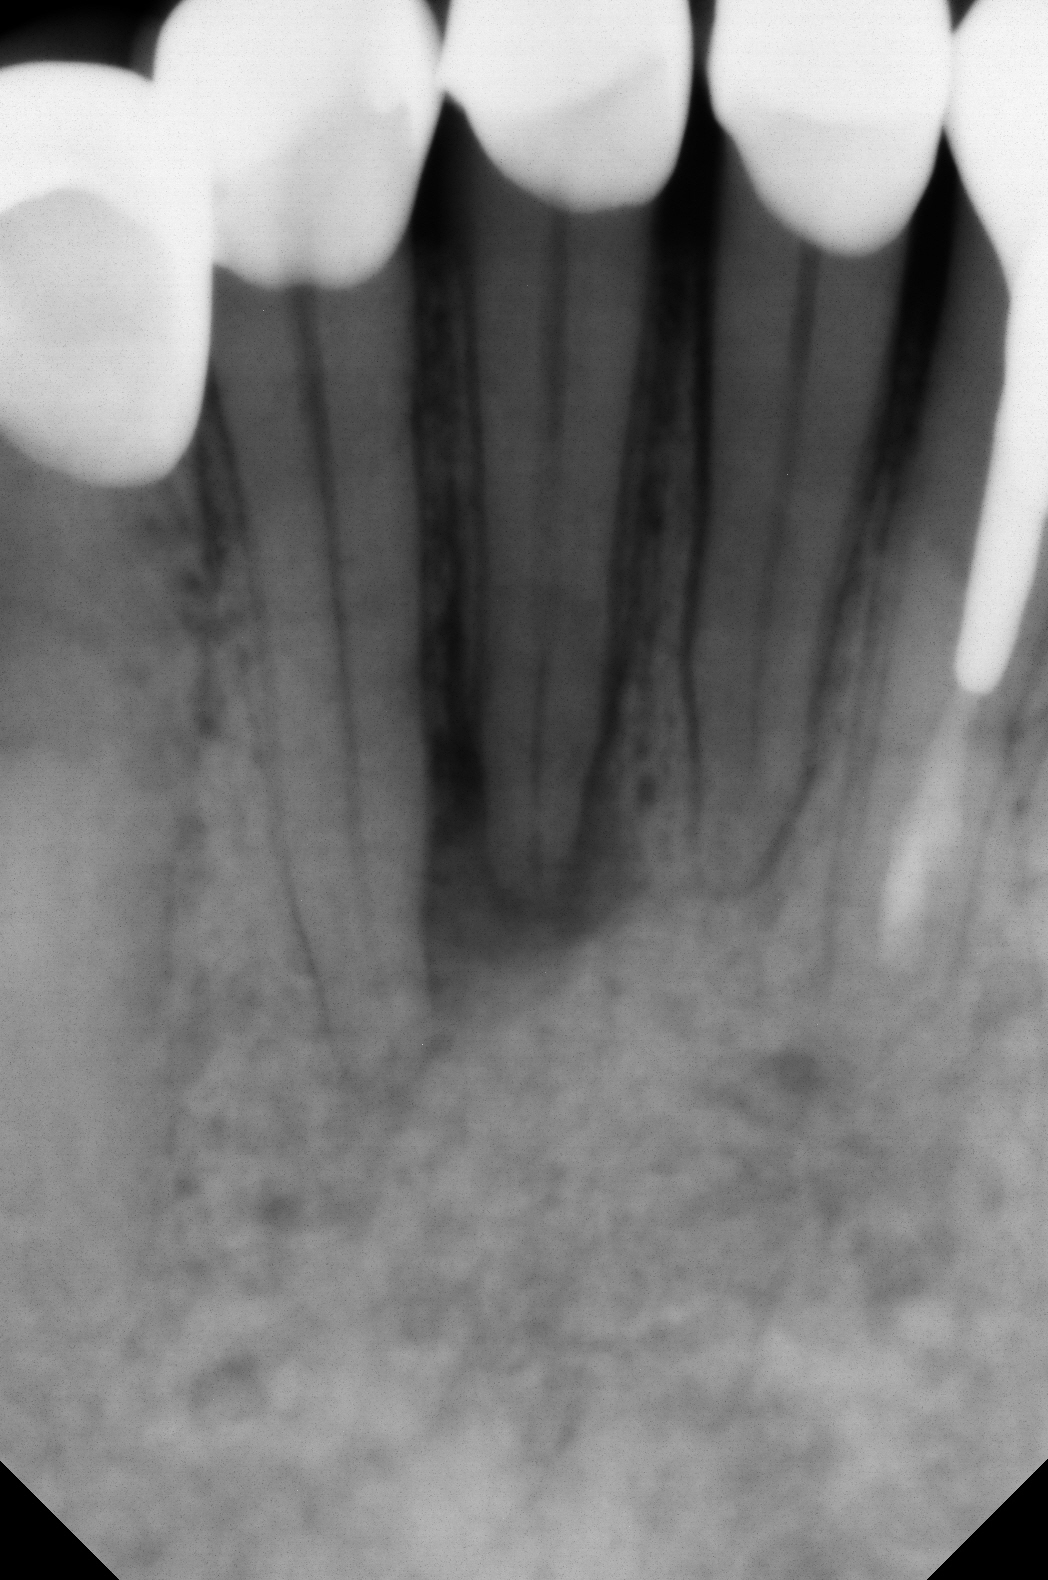

Thought we would try some practice on JK’s challenge to do a DME on a #2 so I created a deep DO alloy on one of our cadavers and then tried to prep it using his technique.

Not perfect, but we are getting better at it. A couple of things:

1. This is way easier using Tytin alloy. It just cuts so much easier than our other alloy.

I let it set about 10 min before cutting.

2. I was hubbed out on my diamond and it was very hard to see anything because of the handpiece head. One needs a longer bur to do these.

3. I switched to a CT-4D and UT-4D to do the final feathering at the base and in my hands, this is far preferable just because you can see so much easier with little risk of ditching the alloy. Maybe others with better bur skills will disagree but I know how I am going to do mine in the future.

4. Joy seemed fine with her positioning with the Stropko—no real adjustments to how we normally function as far as I can tell.

Always looking for help on how we can improve.